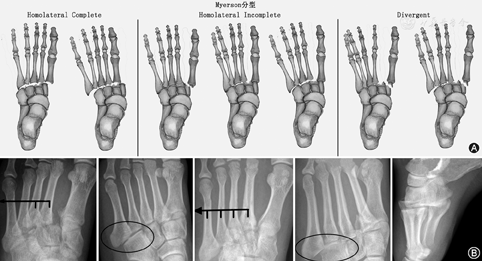

Lisfranc关节骨折脱位患者按Myerson分型[3],(1)Myerson Ⅰ型/同向性脱位分为:①全内侧移位,②全外侧移位;(2)Myerson Ⅱ型/独立性脱位分为:①M1(第1跖骨)内侧移位,②M2~M5(第2~5跖骨)部分骨外侧移位,③M2~M5全外侧移位;(3)MyersonⅢ型/异向性脱位分为:①M1内移、M2~M5部分骨外移,②M1内移,M2~M5全外移,轻度损伤按Nunley-Vertullo分型,Myerson分型(121例),其中Ⅰ1~3型分别为0、16、0例,Ⅱ1~3型分别为14、73、13例,Ⅲ1~2型分别为2、3例。Nunley-Vertullo分型(32例),其中Ⅰ型(M1~2≤2 mm)7例,Ⅱ型[5 mm≥(M1~2)>2 mm]24例,Ⅲ型[(M1~2)>5 mm且足弓塌陷]1例[4]。

采用单盲法,将收集的图像编号后,由未参加收集样本、未得知研究内容的两名骨关节诊断医师(工作经验5年以上)分别对X线、CT、MR图像进行依次观察诊断,观察内容包括骨折部位、有无脱位及脱位方向、足弓情况、足踝韧带损伤等情况,结果记录并整理,两者有异议处经商讨后统一,最后以正常Lisfranc关节形态及排列(图1)做对照,根据Myerson分型和Nunley-Vertullo分型[1]将损伤分型。统计学分析使用SPSS 17.0,描述性分析采用

Lisfranc关节损伤患者的初诊X线漏总诊率为14.9%(18/121),其中99例Myerson型损伤漏诊率为7.1%(7/99),而漏诊的7例患者均发生在Myerson Ⅱ型患者中;另外22例Nunley-Vertullo型损伤中漏诊率为50%(11/22),两者比较差异有统计学意义(P=0.016)。骨折脱位者正位上表现为M2基底部榫眼样凹槽结构消失,M2基底部变浅,M1~M5的一根或多根向内侧或外侧移位(图2),Ⅰ型13.1%(13/99),Ⅱ型82.8%(82/99),Ⅲ型占4.1%(4/99)。99例患者中M2外移位占75.8%(75/99),关节间隙>2 mm者(图3)占67.7%(67/99),平均为2.0~18.5(4.6±2.5)mm,其余患者间距<2 mm。99例患者中第1跖骨基底部与第2跖骨基底部间存在小骨片/小斑片征(Fleck)者(图3)为47.5%(47/99),行足侧位负重或非负重X线可显示M1~M5中的一根或多根相对于楔骨的背或跖侧移位,99例患者中44.4%(44/99)存在背侧移位,6.1%(6/99)为跖侧移位,跖骨侧脱位可导致X线图像上Myerson分型的不典型,50例移位者中累及M2基底部者占90%(45/50)。22例Nunley-Vertullo型损伤患者中Nunley-Vertullo Ⅰ型为5例,Ⅱ型为16例,Ⅲ型为1例,17例患者M1~M2间隙增大2 mm,平均为2.3~6.2(4.0±1.1)mm,间隙间存在小骨片患者占45.5%(10/22),只有1例患者即Ⅲ型者存在M2背侧移位,余未见背侧或跖侧移位。本组中<18岁患者,6例患者行X线检查,但仅2例可观察到骨折线穿过骺线同时累及骨骺与干骺端,2例患者M1~M2间距>2 mm,2例患者Fleck征阳性。

Lisfranc关节为中足与前足的重要分界和连接。从功能和解剖结构来看,Lisfranc关节关节面连线为"S型",被分为"三柱",内柱为C1-M1相关节,中柱为C2-C3-M2-M3相关节,外住为Cu-M4-M5相关节,M1-M5基底部横弓似"罗马拱桥",此弓主要靠M2基底部维持,故此M2又称为"基石"(key stone),X线足正位成像上,M2插入M1、C1-3、M3构成的"榫眼"样凹槽中,此结构称为榫眼关节(mortise joint),M2与M1基底部高度相距1 cm,M2与M3基底部高度相距0.5 cm[5,6],而M1~M2基底部水平距离应<2 mm(图1),凹槽的深度对关节稳定性亦起到重要作用,Mortise关节凹槽的变浅是Lisfranc关节损伤的危险因素之一[7]。